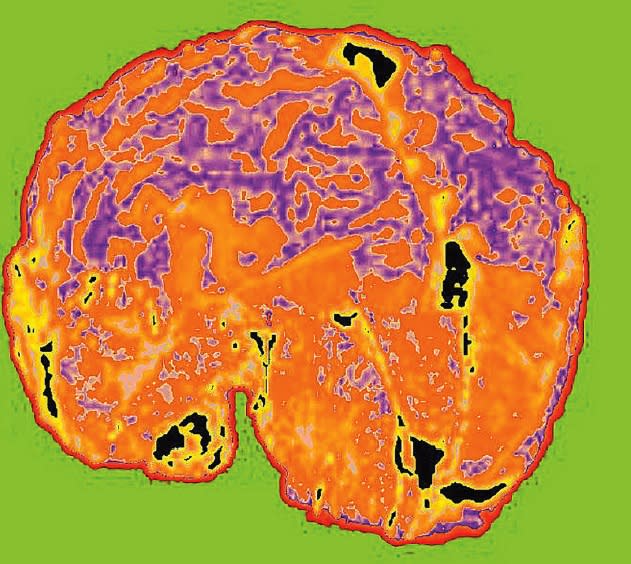

In 2002, NASA’s Goddard Space Flight Center issued a nonexclusive license to Bartron Medical Imaging (BMI) LLC of New Haven, CT, which quickly realized that RHSEG was the solution they needed to differentiate difficult- to-see details from a complex matrix background. Bartron has since developed a product for use in medical imaging called MED-SEG™, and has reported that RHSEG has enabled them to successfully analyze and extract meaningful and significant features from grayscale data previously indistinguishable by the human eye. The clinicians can also isolate one particular area of interest in an image to compare it with many other reference images in databases at other healthcare facilities.

The device is intended to analyze medical imagery from computed tomography (CT or CAT) scans, positron emission tomography (PET) scans, magnetic resonance imaging (MRI), ultrasound, digitized X-rays, digitized mammography, dental X-rays, soft tissue analyses, and moving object analyses. The technology is also equipped to evaluate soft-tissue slides such as Pap smears for the diagnoses and management of diseases. The advanced image segmentations produced by the RHSEG software allow the MED-SEG system to bring out details in these tests not previously seen with the naked eye. This allows for quick and accurate diagnosis of diseases. Additionally, unlike some other image-analysis devices, MED-SEG does not manipulate the image, so what the physician sees is truly what is there, providing truer images than many other imaging techniques.

Although there are various other potential applications for the MED-SEG system, Bartron has chosen the initial focus of its marketing efforts to be directed toward mammographic soft tissue imaging. It usually takes at least three to five years from the first spot of cancer until its detection, even with regular mammograms. In conjunction with digital mammographic modalities, the MED-SEG system is anticipated to offer a non-invasive, more precise method through analysis of shifts of pixel accumulation and concentration to specific breast areas. Image processing correlated with known breast disease pixel patterns such as calcifications, masses, or distortions may be identified long before they become visible on a mammogram.